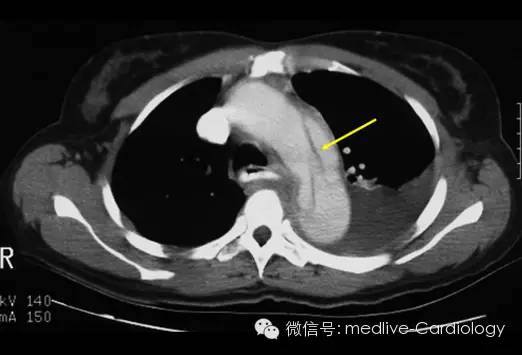

突然发作的胸痛可能是急性主动脉夹层的表现。主动脉内膜一处微小撕裂便可以快速将主动脉壁剥开,并迅速扩展形成假腔(黄色箭头),即使及时诊治,也可能出现致命危险。

CT扫描是另一种快速而准确的诊断手段,其敏感度和特异度都超过90%。增强CT扫描可以确定夹层扩展范围,观察到将主动脉腔分为两部分的内膜层(黄色箭头),以及识别哪些分支血管血流已中断。采集到的图像还可以到工作站进行三维重建,从而对制定外科手术方案起到辅助作用。后续的检查可以用来观察患者术后情况及评估术后并发症。